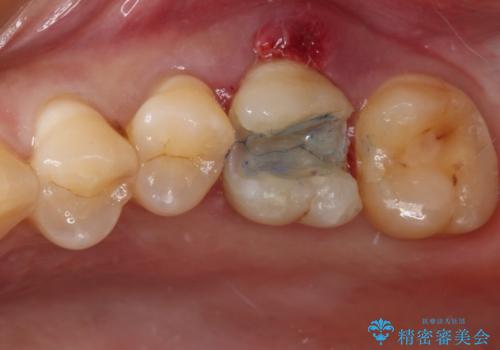

初診時の診察所見では、破折の可能性は低く、根管治療を前提とした治療にて説明をしておりました。

詰められた材料や壊死した組織を除去したところ、鮮明な破折線が認められたため、速やかに抜歯し、傷や骨の治癒を待って、サイナスリフトにより骨高さの低い部分にインプラント埋入を行いました。